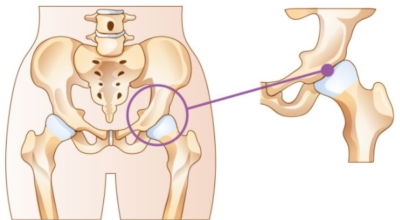

고관절이란 골반을 지탱하는 관절로서 근육과 힘줄로 구성되어 있습니다. 학계에서는 고관절을 엉덩이 관절이라고 부르기도 하며 인체의 하중을 지탱하는 아주 주요한 관절입니다. 각별히 고관절은 우리가 정상적으로 서있거나 움직일 수 있게 만들어주고 달리기, 점프, 무거운 무게를 들 때 최대 체중의 2~10배 가량의 하중을 받기 때문에 적절한 관리가 필요해요. 오늘은 고관절에서 생기게 될 수 있는 고관절 통증 증상에 대하여 알려드릴게요.